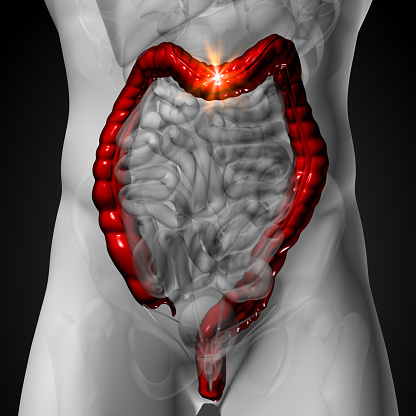

췌장은 소화 효소와 인슐린을 분비하여 소화와 혈당 조절에 중요한 역할을 합니다. 췌장에 문제가 생기면 소화 효소의 분비가 줄어들어 소화불량이 발생할 수 있습니다. 이 경우 복부 통증, 황달, 체중 감소 등의 증상이 동반될 수 있습니다. 특히 소화가 잘 되지 않고 체한 듯한 느낌이 자주 나타난다면 췌장암을 의심해볼 필요가 있습니다.

최근 통계에 따르면, 췌장암 환자는 매년 증가하고 있어 주의가 필요합니다.